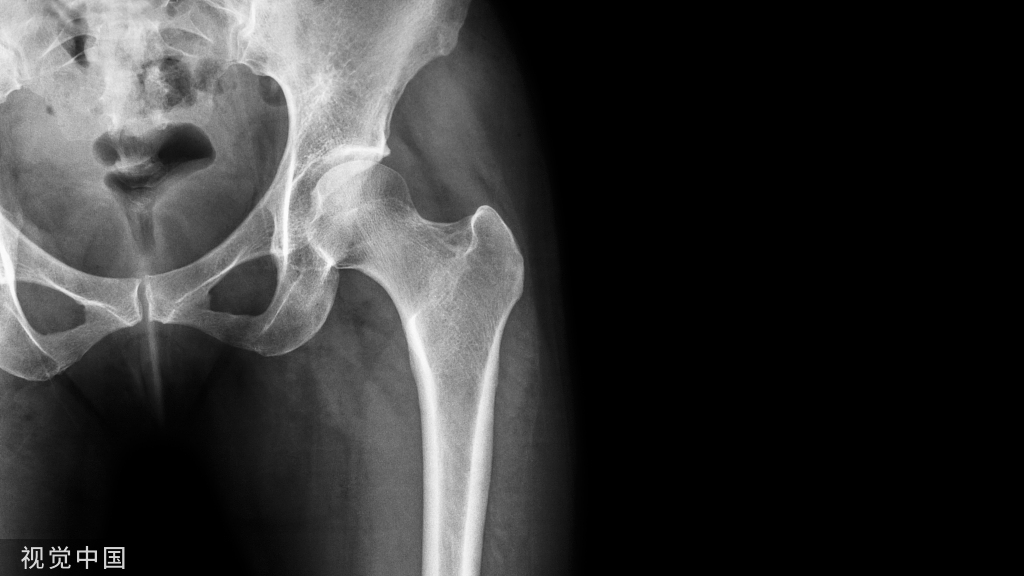

髋关节静力学

(1)双腿站立时的静力学分析

两腿站立期间,髋关节周围没有肌活动产生力矩,关节作用力的计算变得简单:直立时每个股骨头上作用力的大小是人体重量的1/2,因为每个下肢的重量是人体重的1/6,每个髋关节上的作用力将是剩下2/3的1/2,或是体重的1/3;如果髋关节周围肌收缩阻止摆动并且保持身体的直立姿势,这个力的增加将与肌活动的数目成正比。

(2)单腿站立时的静力学分析

单足站立时,站立侧股骨头承重为体重的4倍。这就是Pauwels理论的主要内容。

髋关节动力学

(1)行走时股骨头上产生的关节反应力

行走时,股骨头受力受步行加速度的影响。正常情况下,在步行的支撑期足跟着地时,股骨头受力约为体重的5.8倍。在跑、跳时,股骨头的承重可达体重的10或10余倍。因此,股骨头具有繁重的承重功能。